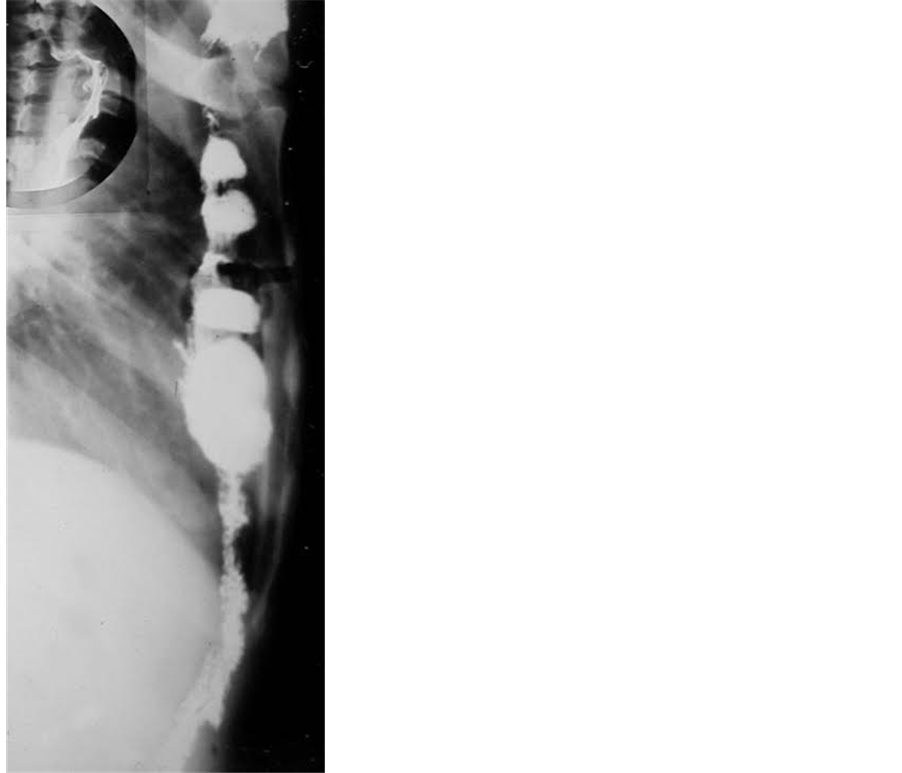

Figure 6. Illustration of the long isoperistaltic graft used in this series.

For total by-pass the graft of choice is a transverse colon segment, pedicled on the left colic artery (Figure 6) which is a more constant artery than the middle colic one [13] [14] . Its mobilized long trunk permits a high gastric anastomosis, while the multihaustral propulsive contractions of this smaller size, active isoperistaltic colonic segment, proved to be a basic factor to prevent gastrocolic reflux [11] [18] [19] . It is well none, that reflux is common after an anisoperistaltcally fashioned graft [2] . We never observed mediastinal compression symtoms, and also incidence of the cervical leaks is fewer [4] [10] than after ileocolic grafting [10] . The smaller diameter of the paraileal vascular arch than that of paracolic one and the disfunction of the Bauchin valve may be an explanation [20] .